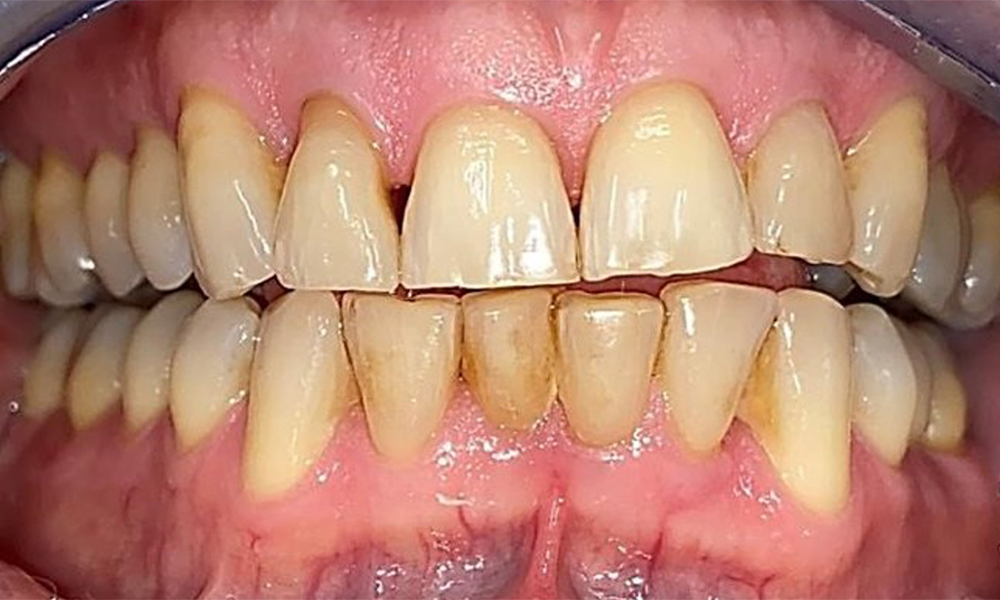

Frontal view with loss of the interdental papillae between 12 and 11.

Fig. 2 Frontal view with loss of the interdental papillae between 12 and 11. © Dr R. Krapf

The patient has a full dentition with 28 teeth, which includes amalgam and composite fillings in the molar and premolar regions. There is a visible clinical marginal gap present on tooth 14. Tooth 27 has an adequate gold inlay. There are also generalized attritions and abrasions. (Fig. 2, Fig. 3, Fig. 4, Fig. 5, Fig. 6)

Periodontal findings

The patient has stage II, grade B periodontitis (5). At 1 to 3 mm, the clinical probing depths were within the physiological range. Localized probing depths of 5 mm were observed on the mesiopalatal aspects on both 17 and 27. There are generalized recessions of 1–3 mm with partial loss of the interdental papillae (Fig. 2, Fig. 3, Fig. 4)